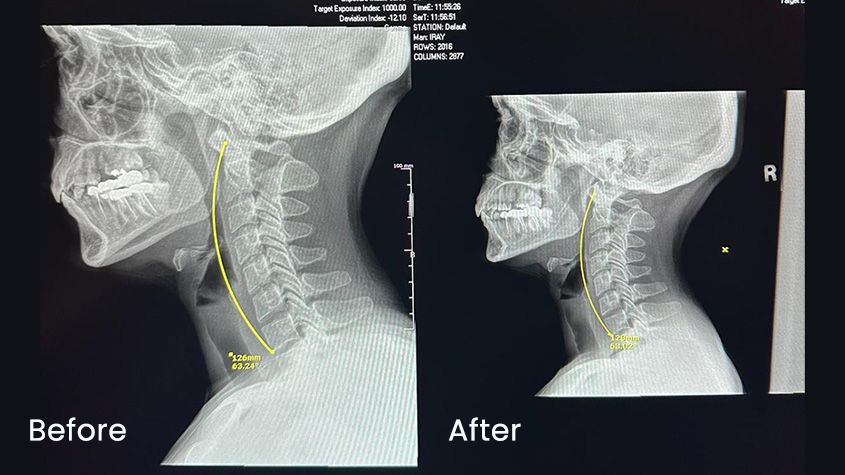

Many of our patients come in because of poor neck posture.

With proper alignment, posture improves, tension decreases, and people often experience fewer migraines, less pain, and a noticeable correction of the forward-neck and hunchback position.